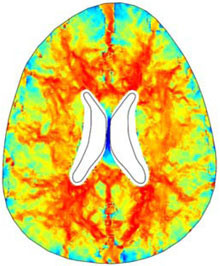

A numerical finite element model of one human brain is built in COMSOL in order to study a particular form of hydrocephalus, the so called Normal Pressure Hydrocephalus (NPH). The geometry of the ventricles and the skull is obtained by Magnetic Resonance Imaging (MRI) and imported in ... Mehr lesen